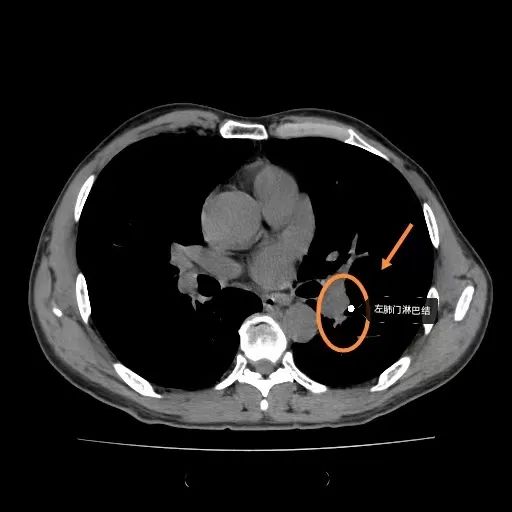

胸部CT

左肺门淋巴结